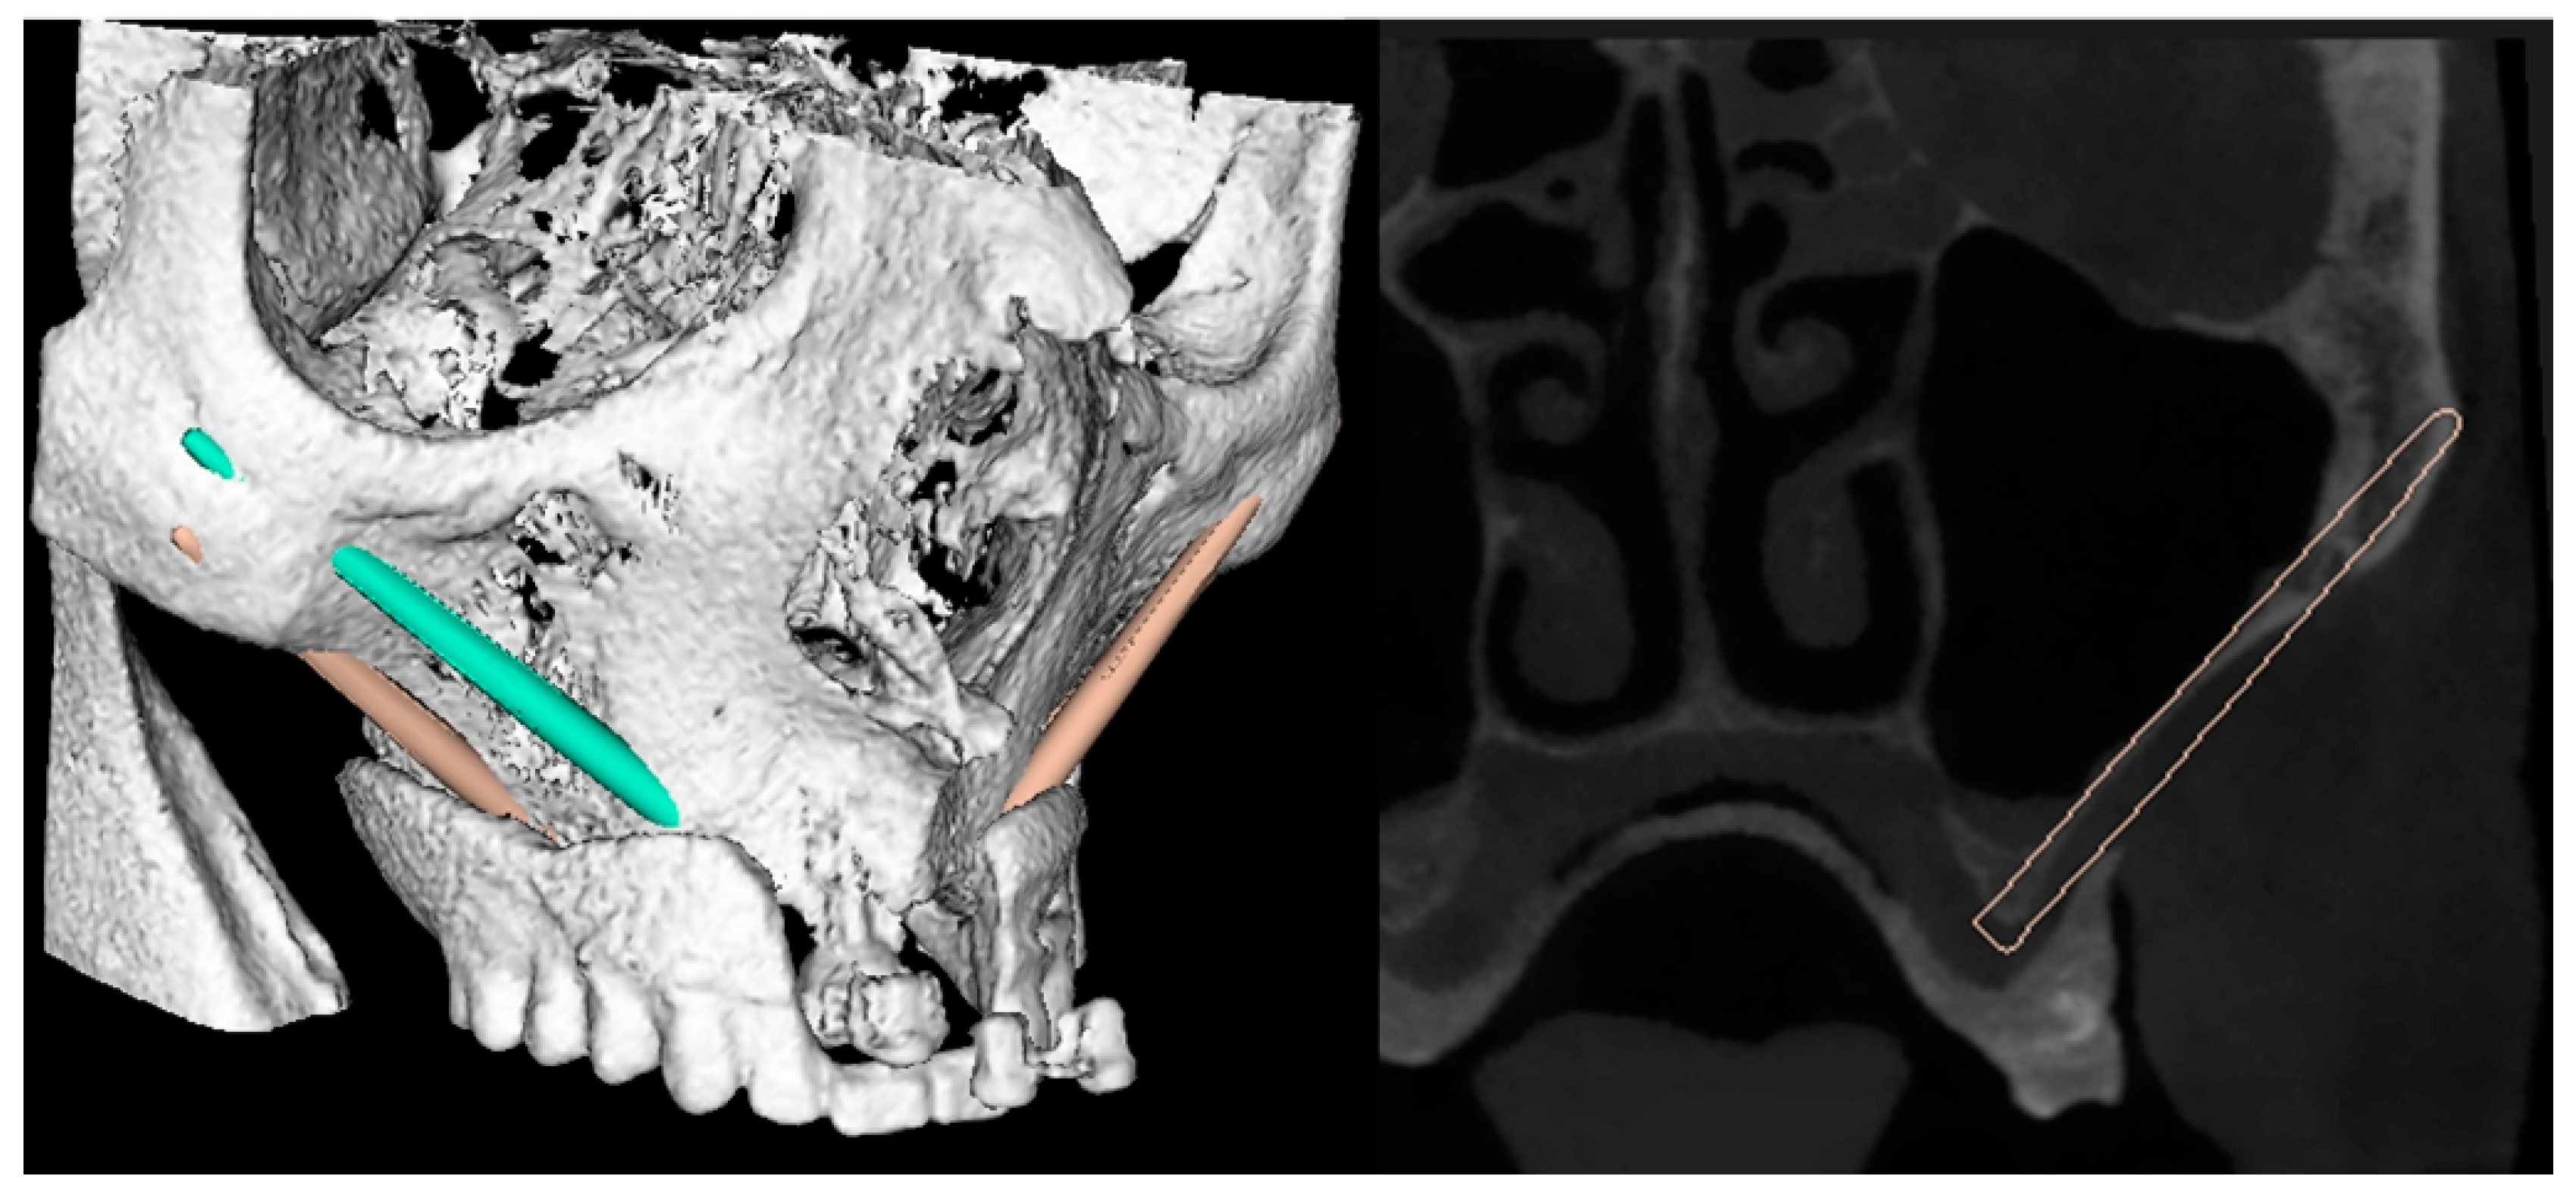

- Step 1. Scanning of the patient and the scan prosthesis/registration template, external registration frame, or bone markers.

- Step 2. Software planning of the implant position.